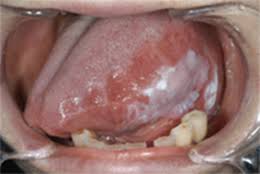

혀 백태는 혀의 표면에 하얀색 또는 노란색의 얇은 막이 형성되는 증상으로, 일반적으로 구강 내 세균이나 죽은 세포, 음식물 찌꺼기 등이 쌓여 발생합니다. 이는 구강 위생이 불량하거나 면역력이 저하된 경우에 더욱 두드러지게 나타날 수 있습니다.